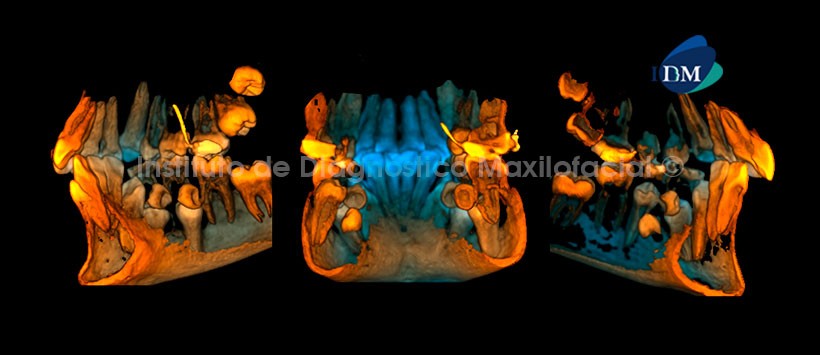

En las reconstrucciones 3D se observa de manera ilustrativa y detallada la ubicación exacta de todos los supernumerarios así como la repercusión de estos con las estructuras óseas y dentales adyacentes. También cabe mencionar que las reconstrucciones 3D que nos brinda el software Romexis nos sirve de mucha ayuda para una posterior explicación tanto al odontólogo como al paciente. (Figura 5 y Figura 6)